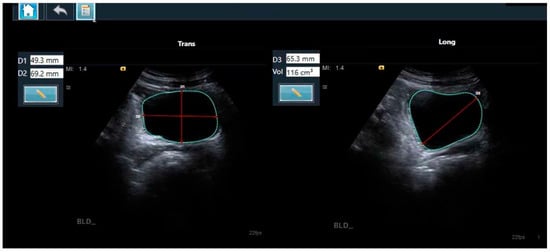

2.4. The Two-Dimensional Ultrasound-Based Bladder Volume Calculation Method

2.5. The AI-Based Module